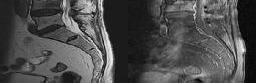

Figures 1 and 2 show sagittal and axial MRI from an 83-year-old woman with an ataxic gait, loss of dexterity, and intermittent loss of bowel and bladder control. The symptoms have been getting progressively worse over the past several weeks.

What disease process is most likely the cause of the patient’s symptoms?

4. Pigmented villonodular synovitis Discussion: B

The patient has a pannus at the C1-2 articulation that is compressing the spinal cord and causing myelopathy symptoms. The development of a pannus at this location has been associated with rheumatoid arthritis. Steinberger and associates showed increased morbidity and mortality when using an anterior approach and the surgery took longer than 4 hours. Chieng and associates showed better outcomes and lower complications rates using a posterior approach.

CLINICAL SITUATION

Discussion: A